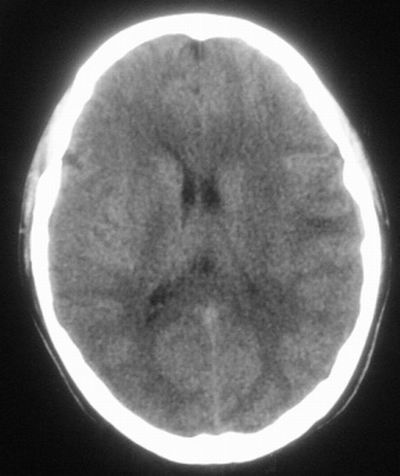

治疗三天后复查ct片示:

治疗三天后复查ct:除左侧额顶叶血肿外。左侧额叶另见片状低密度灶,密度不均匀,境界不清;考虑脑梗塞。

建议:必要时行进一步检查排除烟雾病。